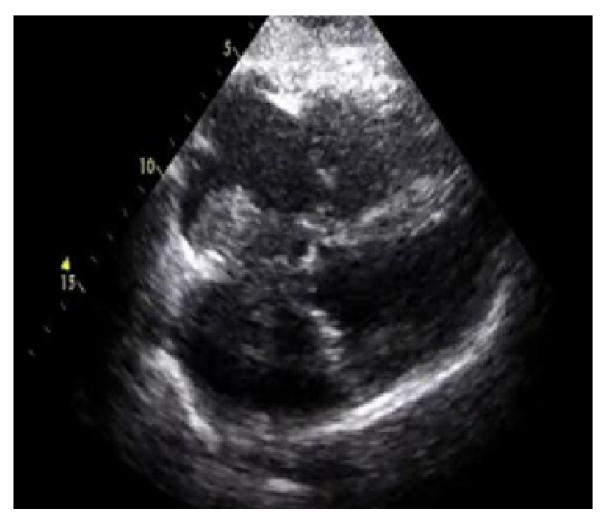

The numerical outcomes of the proposed as well as existing techniques are presented in this section. The input image of echocardiograms is given in Figure 4, and the pre-processed image is given in Figure 5. The FCM based segmentation is accomplished in echo images that is illustrated in Figure 6.

Figure 5.

Output of the pre-processed image.